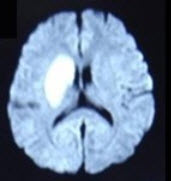

男性,65岁,有高血压病史5年,因左侧肢体无力1天入院摔,行头颅MRI出现如图所示病变,应诊断为( )

A:多发性腔梗

B:蛛网膜下隙出血

C:脑梗死

D:硬膜下出血

E:脑出血